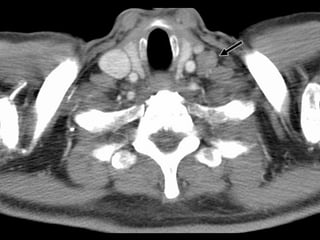

1. Highest mediastinal LNs

Upper border: lower border or cricoid.

Lower border: upper border of manubrium

and clavicles.

Medial border: medial edge of CCA.

Lateral boder: first rib.

1. Highest mediastinalLNs Upper border: lower border or cricoid. Lower border: upper border of manubrium and clavicles. Medial border: medial edge of CCA. Lateral boder: first rib.